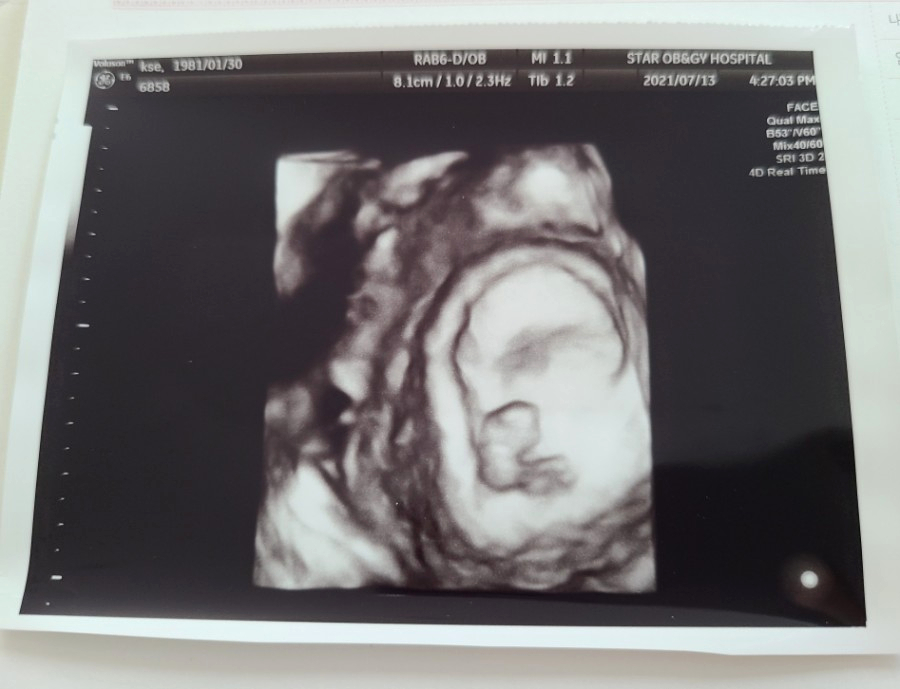

아무튼 7월 13일을 기준으로 전 8주 차가 되었다고 하셨고 이날 처음으로 아기의 심장박동을 확인할 수 있었어요.

심장소리를 들으니 진짜 괜히 뭉클해지더라고요. '내 배속에 정말 생명이 있구나!'란 사실이 그제야 실감 난 것 같아요.

아기의 크기는 1.67CM. 이날 아기의 얼굴과 몸도 초음파로 볼 수 있었어요.